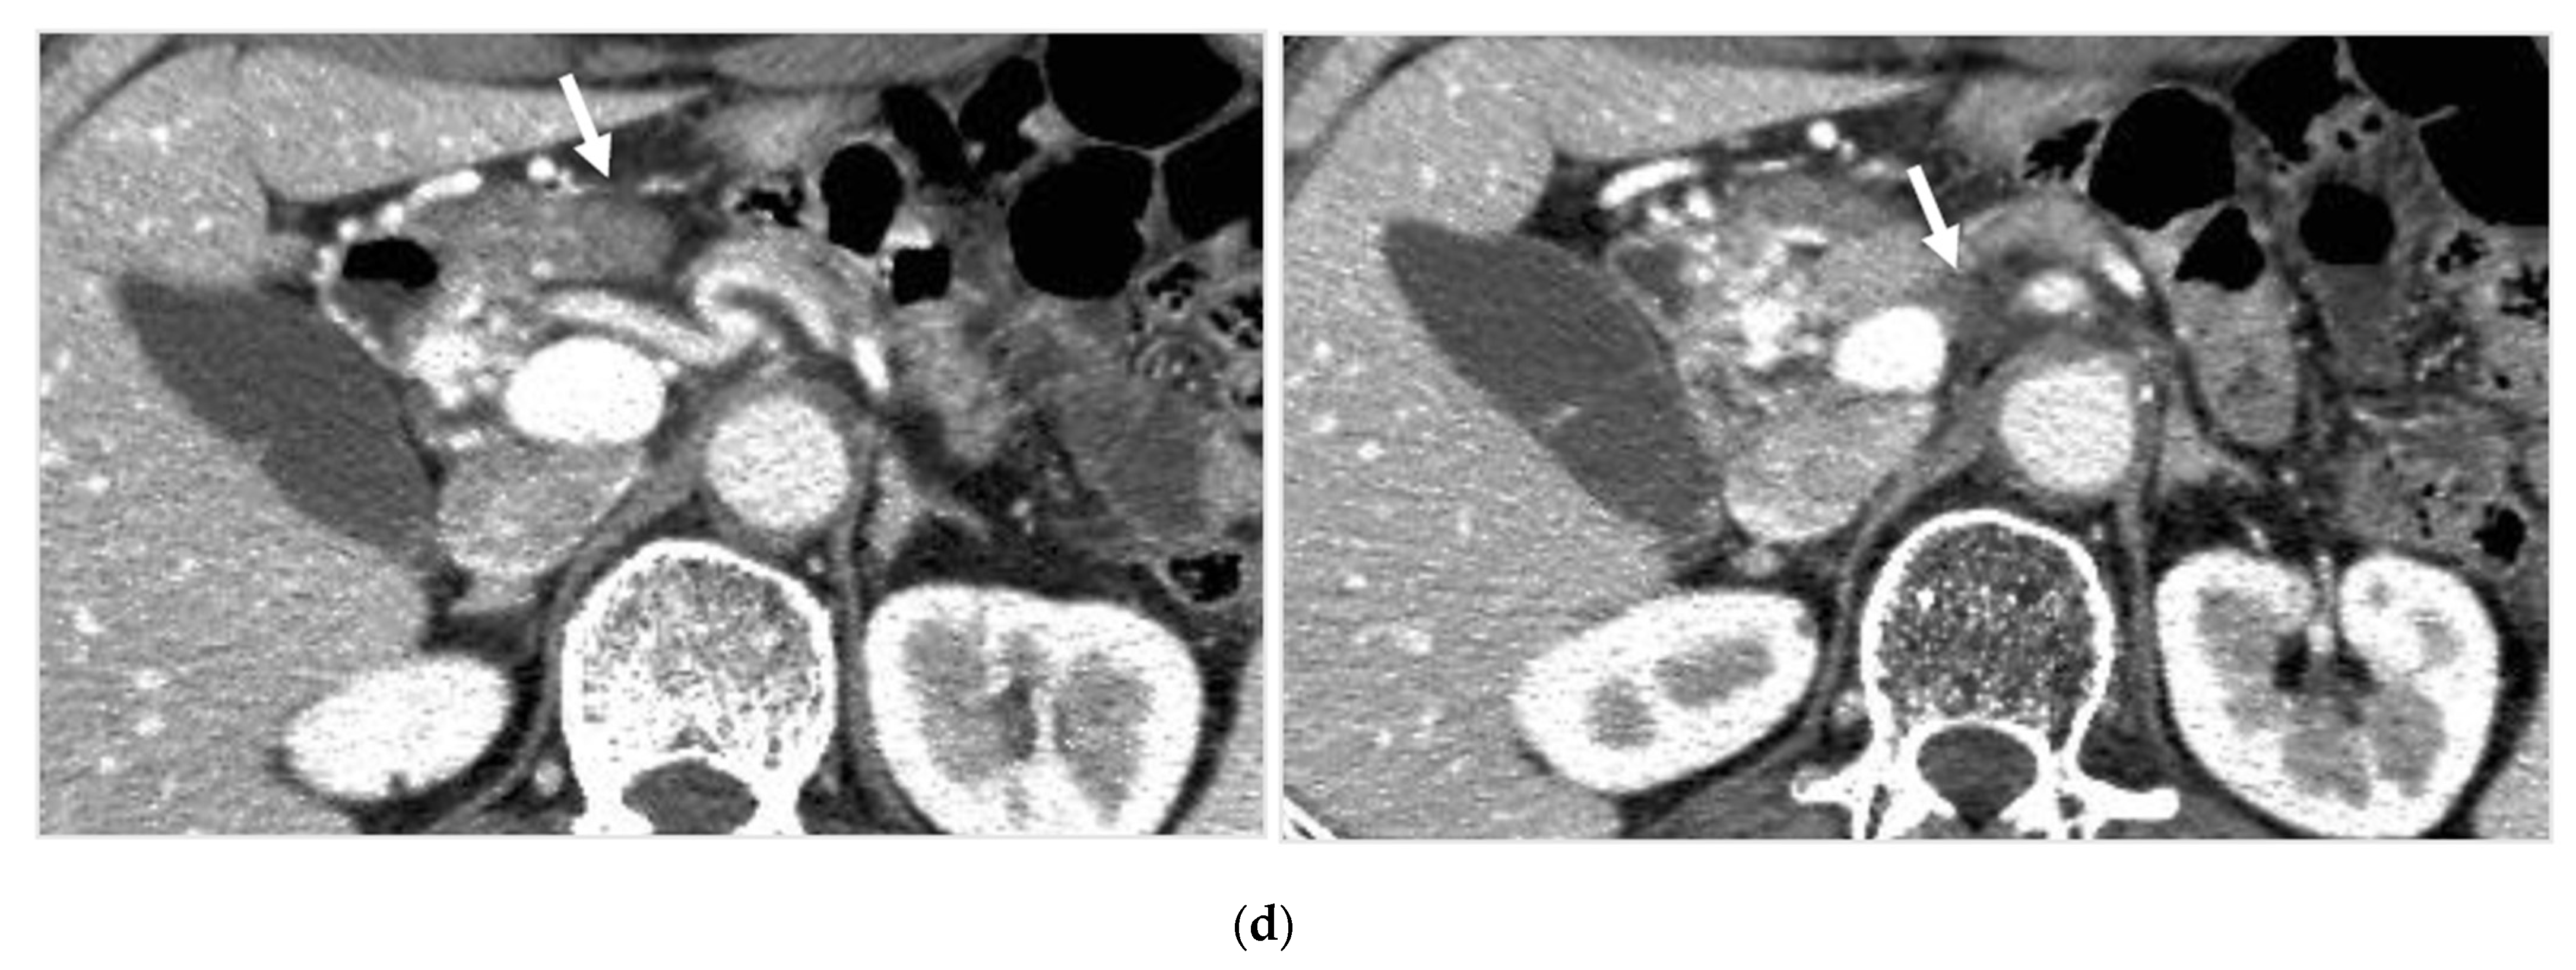

Identifying Supplying Arteries to Pancreatic Cancer

Method of Arterial Administration of Anticancer Agents